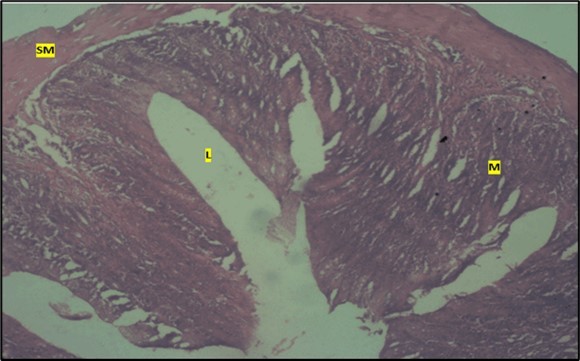

Results from the large intestine histological observation showed normal appearance of epithelial cells lining the mucosa with no pathological observations in control animals (Figure 5). However, administration of Abelmoschus esculentus at low dose showed dysplasia of cells and loss of normal epithelial shape (Figure 6) and the high dose group showed mild dysplasia (Figure 7)

Figure 6.Low dose showing the lumen (l), smooth muscle layer (sm) and dysplasia of the mucosa (m). there is loss of epithelial shape H & E. X40.